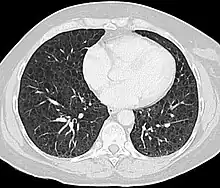

Computed tomography

The high-resolution computed tomography (HRCT) chest scan is better than the chest radiograph to detect cystic parenchymal disease and is almost always abnormal at the time of diagnosis, even when the chest radiograph and pulmonary function assessments are normal.[4][6][7][88] The typical CT shows diffuse round, bilateral, thin-walled cysts of varying sizes ranging from 1 to 45 mm in diameter.[6][7] The numbers of cysts varies in LAM from a few to almost complete replacement of normal lung tissue. The profusion of cysts tends to be milder in patients with TSC-LAM than S-LAM, perhaps explained in part because TSC-LAM patients typically receive earlier screening.[12] Pleural effusions are seen on CT in 12% of patients with S-LAM and 6% of patients with TSC-LAM. Other CT features include linear densities (29%), hilar or mediastinal lymphadenopathy (9%), pneumothorax, lymphangiomyoma, and thoracic duct dilation.[6][7] Ground-glass opacities (12%) suggest the presence of interstitial edema due to lymphatic congestion. In patients with TSC, nodular densities on HRCT may represent multifocal micronodular pneumocyte hyperplasia (MMPH) made up of clusters of hyperplastic type II pneumocytes.[80][89][90] MMPH may be present in males or females with TSC in the presence or absence of LAM, but not in patients with S-LAM.[91] MMPH is not typically associated with physiologic or prognostic consequences, but one case of respiratory failure due to MMPH has been reported.[92][93][94]